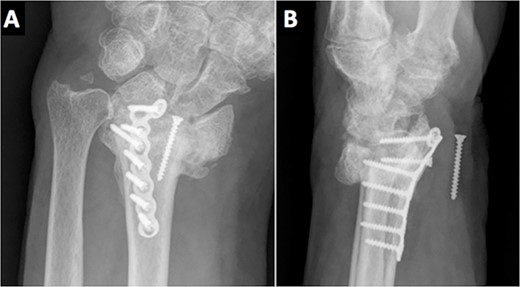

At the 2-year follow-up visit, the fracture had consolidated, both clinically and radiologically. His ranges of movement were 30°–30° of flexion–extension and a radial–ulnar of 10°–15°; all movements were pain-free. His grip strength was 70% of the opposite wrist and he had restarted his job, without complications. The patient continued refusing a new surgery to remove the screw as he was pain-free and performing the activities of daily life without any difficulty.